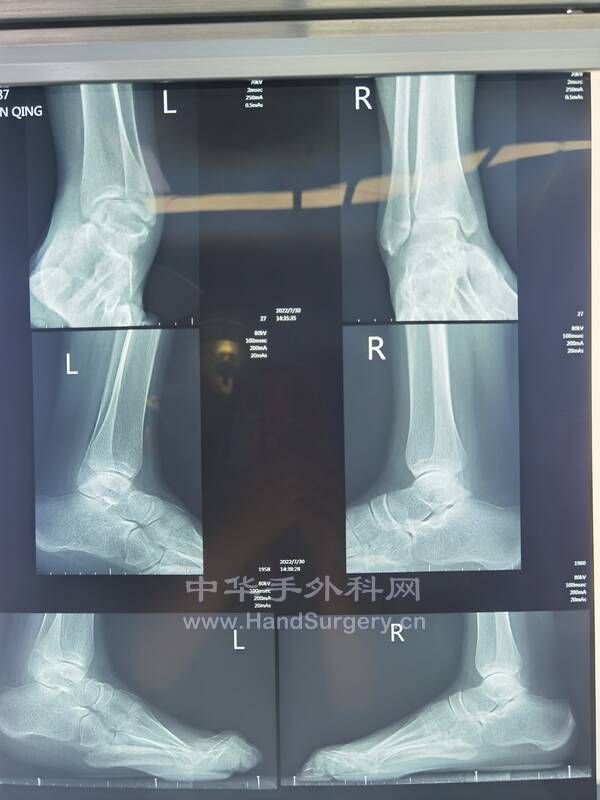

2022-7-24~7-25门诊知识点

4.类风湿性关节炎的患者如果需要手术,必须先确定是否在风湿活动期,询问患者目前的症状和检查血常规+CRP,类风湿因子和血沉,再决定是否可以手术?(3-4)

9.距骨缺血性坏死患者,如果体重超正常体重,建议其减重后再行手术治疗。(5--8)